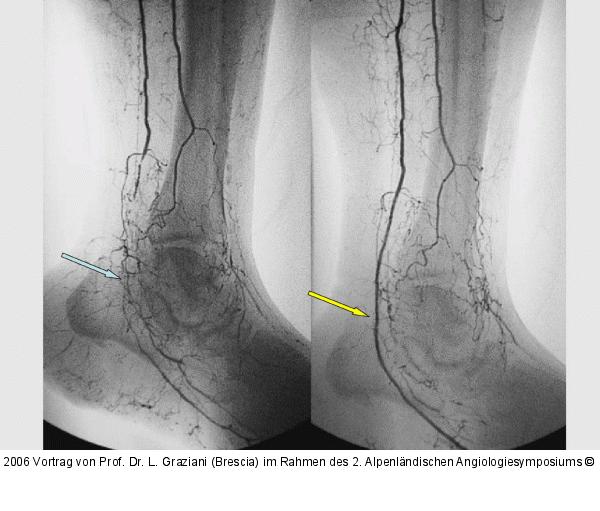

Abbildung 79: Arteria dorsalis pedis - Katheterisation

Arteria dorsalis pedis - Katheterisation